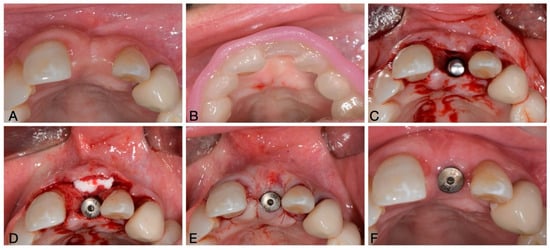

- Puisys, A.; Deikuviene, J.; Vindasiute-Narbute, E.; Razukevicus, D.; Zvirblis, T.; Linkevicius, T. Connective tissue graft vs porcine collagen matrix after immediate implant placement in esthetic area: A randomized clinical trial. Clin. Implant. Dent. Relat. Res. 2022, 24, 141–150. [Google Scholar] [CrossRef]